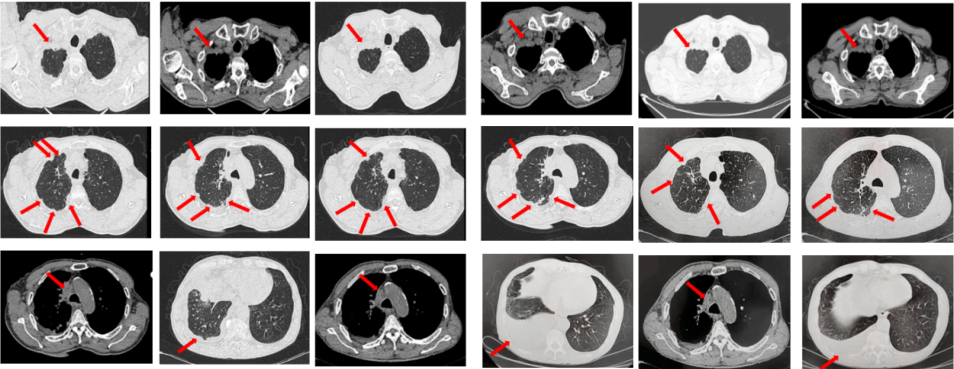

2023年9月复查评效PD。成功入组“一项开放、多中心对比谷美替尼与多西他赛在既往接受免疫治疗和含铂双药化疗后进展的驱动基因阴性且伴有MET扩增的局部晚期或转移性非小细胞肺癌患者中的随机对照III期临床研究”。成功随机到试验组,口服谷美替尼至2024年10月,期间复查最佳评效PR。

图3:A.二线治疗后病情进展,右肺上叶新发肿物较前明显增大,新发无症状脑转移病灶;B.经谷美替尼(300mg po qd)治疗3个月后复查肺内病灶及颅内病灶较前明显缓解

如图7所示,2021年7月复查评效PD。重新行右肺穿刺取得病理,提示腺癌。NGS组织基因检测:MET基因扩增(变异倍数)4.0倍。改行赛沃替尼联合奥希替尼治疗。治疗10日后突发一过性寒战伴低血压,不除外药物相关,对症治疗后好转。复查评效达PR,因患者无法耐受药物不良反应,改行奥希替尼联合克唑替尼治疗至今,定期复查,最佳评效PR,末次评效SD(2024年7月)。

图7:A.奥希替尼治疗后病情进展,右肺内病灶较前再次增大,同时右肺内新发转移灶;B.出现MET扩增后,奥希替尼联合MET-TKI治疗后肺内病灶较前明显缩小;C.当前方案治疗持续有效。